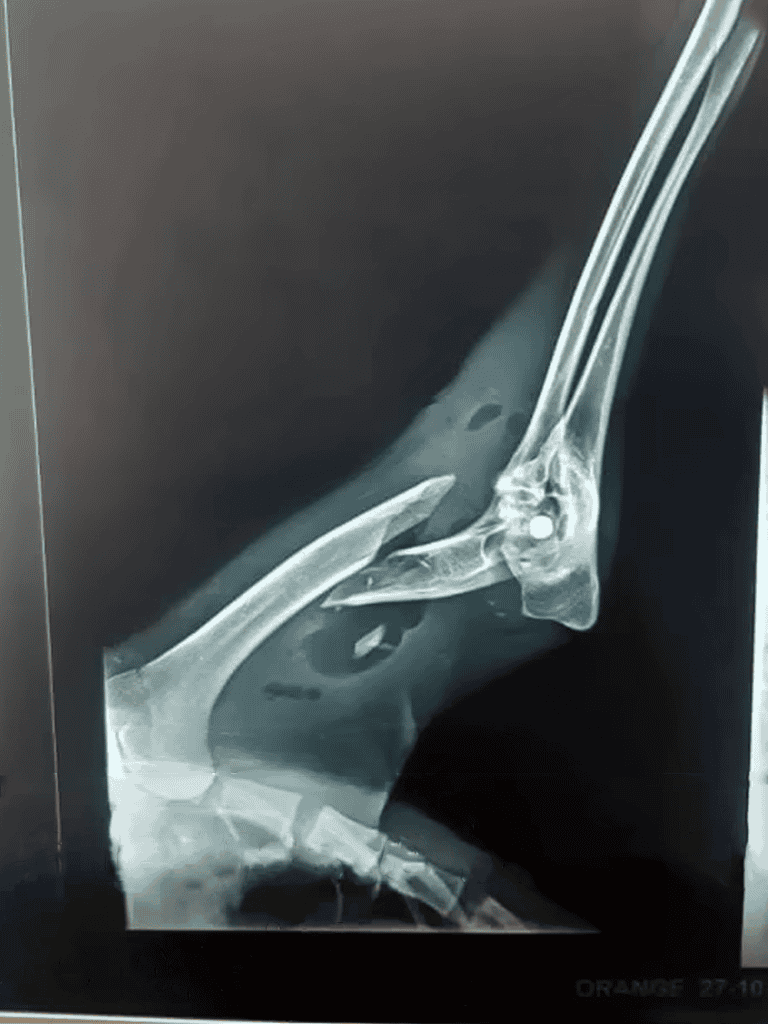

X-rays revealed severe breaks in both front legs.

X-rays showed Cleopatra’s front legs were broken, requiring immediate surgeries with plates and pins for recovery.